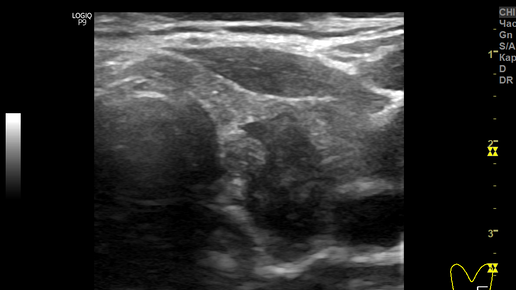

На примере одного из случаев нашей Клиники, расскажу о том, по каким признакам определяется рак в щитовидной железе при УЗИ. В этот раз пациентка обратилась в Клинику только для УЗИ. Каждый раз, начиная УЗИ щитовидной железы, совершенно не предполагаешь что увидишь при исследовании. Так и в этом случае. (Числами я обозначил признаки рака). Провожу датчиком над левой долей железы, просматривая ее методом сканирования, и вижу среди нормальной (изоэхогенной) ткани в нижней части доли темный участок...